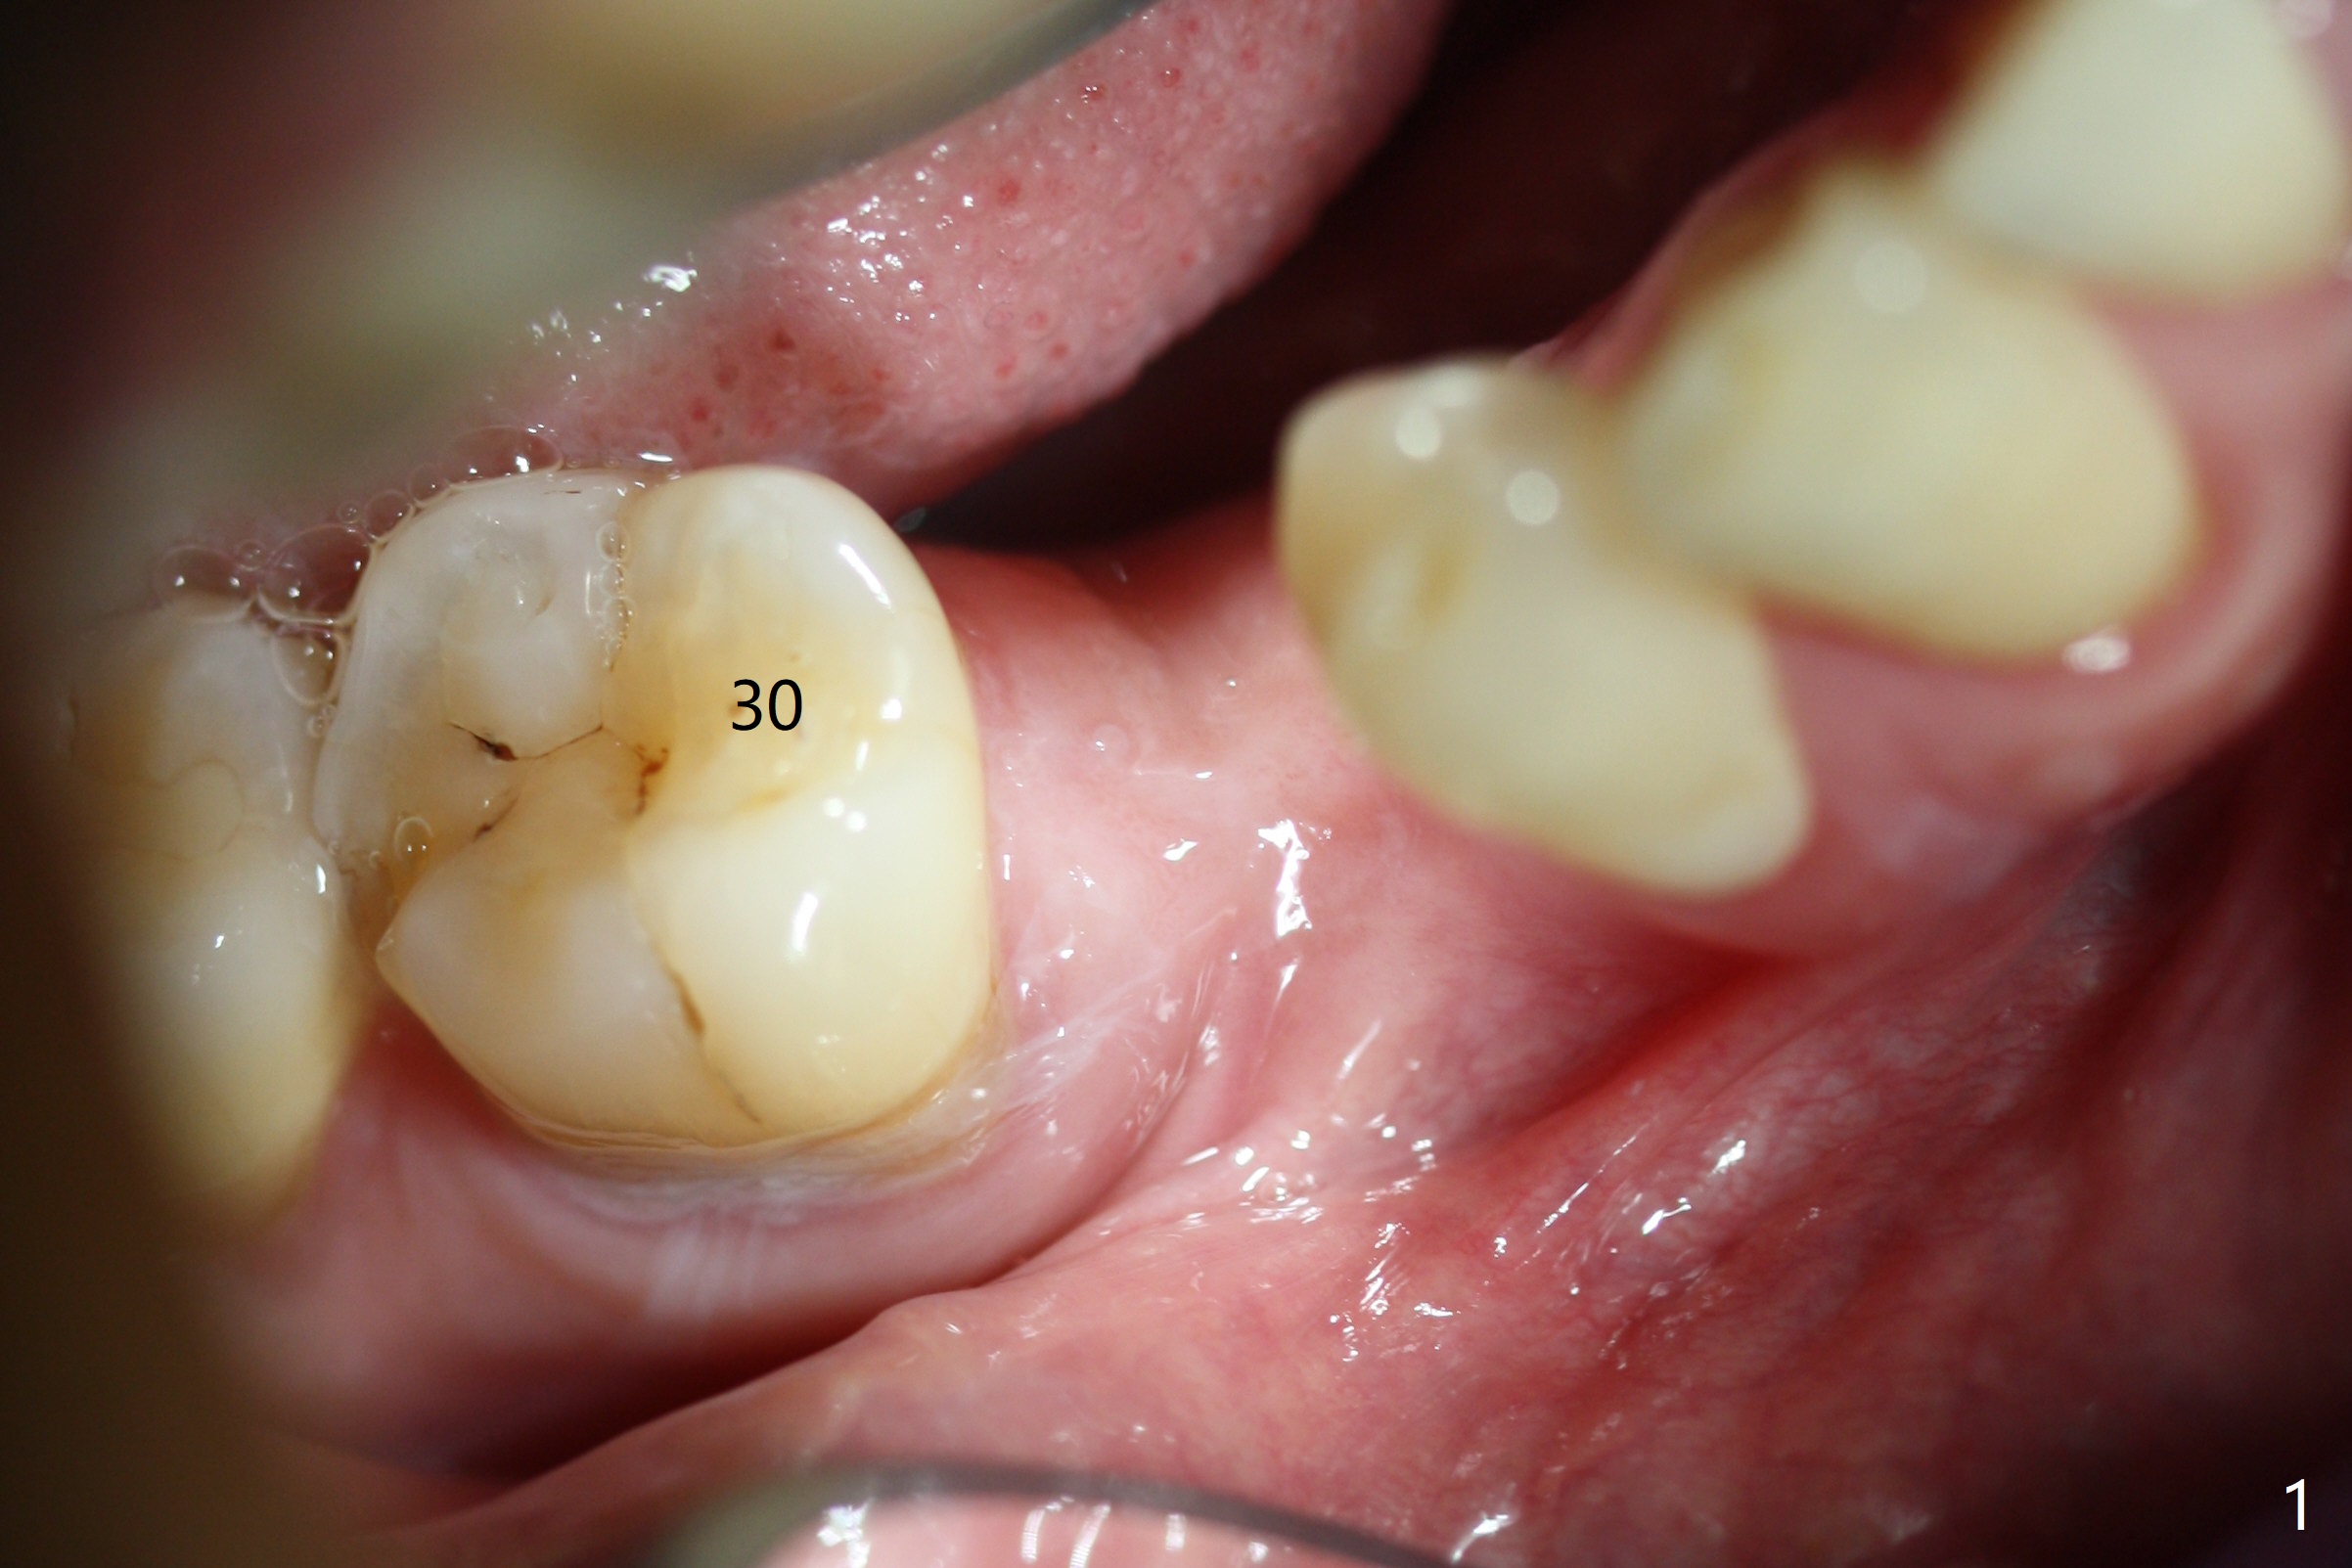

The base of the edentulous ridge at #29 looks wide (Fig.1), but the most coronal portion is the thin soft tissue (Fig.2).  It appears that there has been bone resorption since extraction.  The initial osteotomy depth is 11.5 mm (Fig.3).  Since the Mental Loop seems to be nearby, the depth of subsequent osteotomy (3 mm) remains the same (Fig.4).  Although the final depth of osteotomy is 13 mm, the implant placed is short (3.8x11.5 mm, Fig.5,6), as compared to the immediate implant (3.8x18 mm) at the contralateral side (#20).  There is mild bone resorption mesially 4 months postop (Fig.7).  The crown is loose (poor osteotomy position, guide necessity) 7 months post cementation immediately prior to 18 cementation, although there is no gross bone losss 1 year 7 months post cementation (Fig.8).